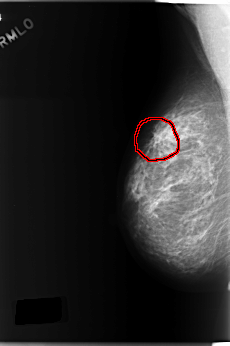

C_0183_1.RIGHT_MLO

RIGHT_MLO LINES 5872 PIXELS_PER_LINE 3896 BITS_PER_PIXEL 12 RESOLUTION 50 OVERLAY

FILE: C_0183_1.RIGHT_MLO.OVERLAY

TOTAL_ABNORMALITIES 1

ABNORMALITY 1

LESION_TYPE MASS SHAPE ARCHITECTURAL_DISTORTION MARGINS ILL_DEFINED

ASSESSMENT 4

SUBTLETY 4

PATHOLOGY MALIGNANT

TOTAL_OUTLINES 1

BOUNDARY